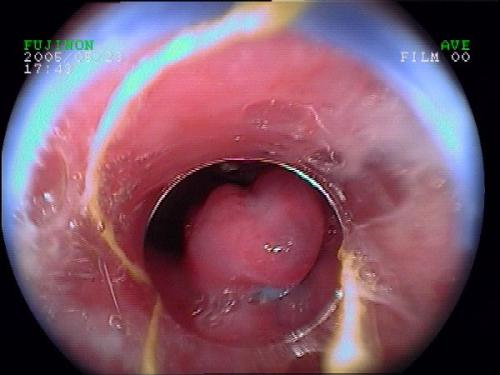

◆ 食管靜脈曲張套扎術(shù)

適應對象:肝硬化門(mén)脈高壓引起食管靜脈曲張出血和可能發(fā)生出血的病人。

療 效:根除曲張靜脈,預防和減少再出血。

食管下靜脈曲張套扎術(shù)

食管下套扎術(shù)